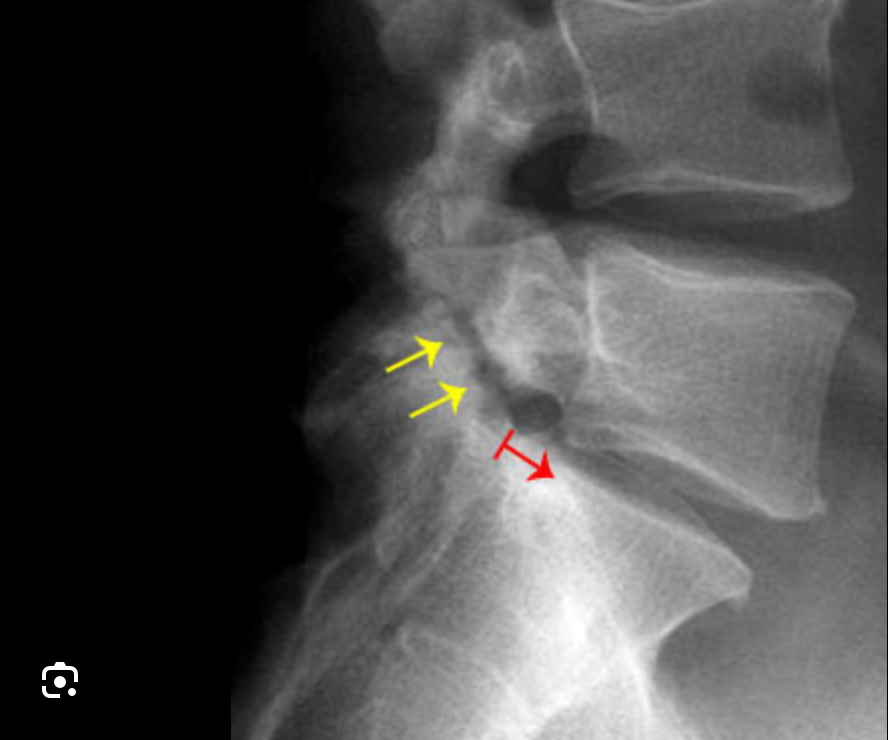

- X-rays – Initial screening (may miss early stage)

- CT Scan – Gold standard for bony defect visualization

Spondylolysis is a condition characterized by a stress fracture or defect in the pars interarticularis, a small but critical portion of a vertebra. It most commonly affects the lower lumbar spine, especially the L5 vertebra, and is a frequent cause of back pain in adolescents, athletes, and young adults.